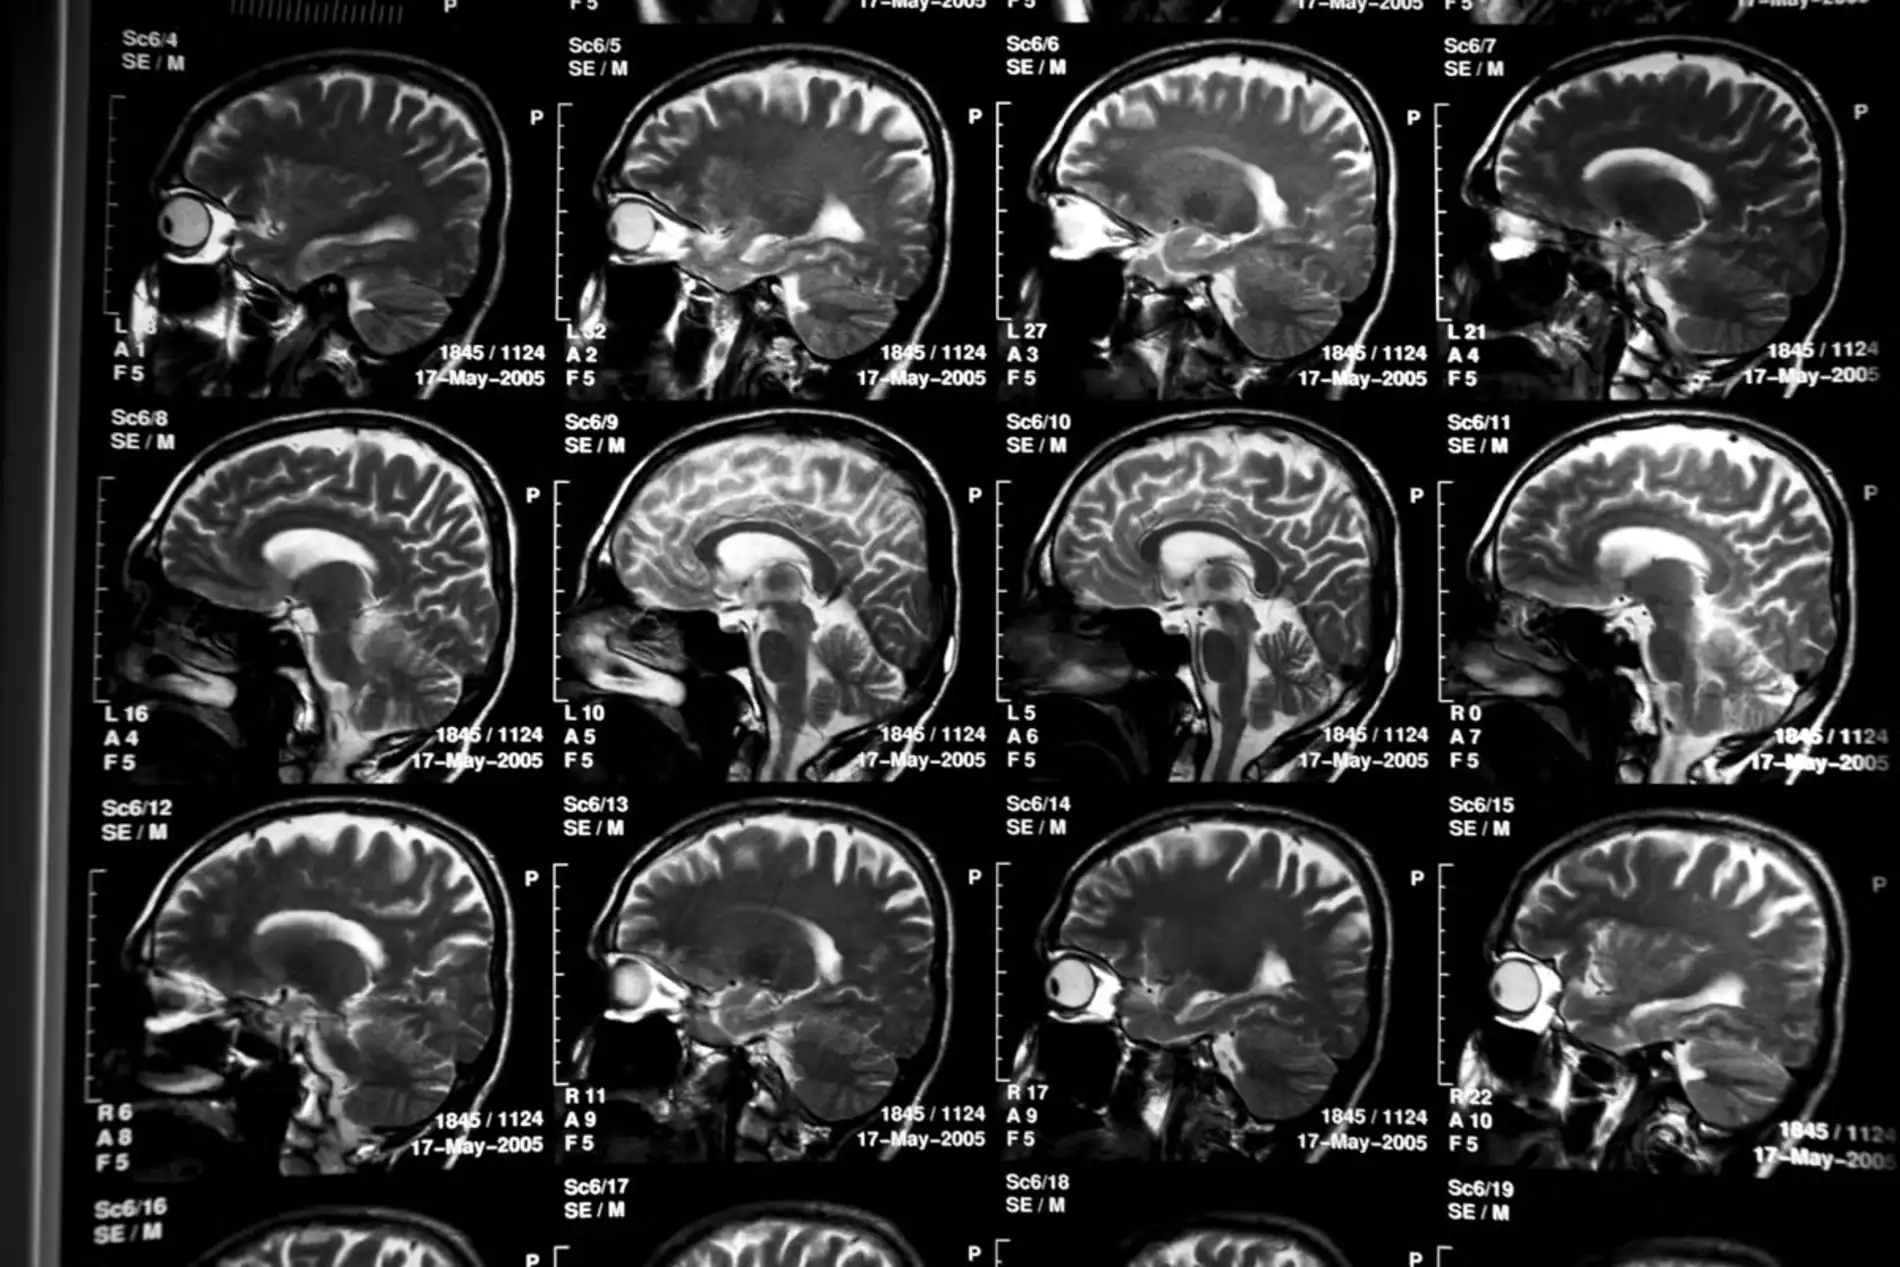

O Alzheimer é uma doença cruel, marcada pela deterioração cognitiva causada por aglomerados de proteína beta-amiloide, que formam placas no cérebro. O Kisunla, desenvolvido como um anticorpo monoclonal, tem um alvo claro: essas placas. Ele se liga aos aglomerados de beta-amiloide, reduzindo sua presença e retardando a progressão da doença, especialmente em pacientes com comprometimento cognitivo leve ou demência leve.

Segundo a Anvisa, o medicamento atua como um “limpador cerebral”, diminuindo o impacto das placas que prejudicam a memória, o raciocínio e a linguagem. Essa abordagem é inovadora porque, ao contrário de tratamentos que apenas aliviam sintomas, o Kisunla busca frear o avanço da neurodegeneração. Para mais sobre a ciência do Alzheimer, confira o site do Alzheimer’s Association.

Nem todos os pacientes podem se beneficiar do Kisunla. A Anvisa alerta que o medicamento é contraindicado para quem usa anticoagulantes, como varfarina, ou tem diagnóstico de angiopatia amiloide cerebral (AAC) identificado por ressonância magnética. Nessas condições, os riscos, como hemorragias cerebrais, superam os benefícios, exigindo avaliação médica rigorosa antes do tratamento.

Outro desafio é a infraestrutura. A administração do Kisunla exige infusões regulares e monitoramento por ressonância magnética, o que demanda clínicas especializadas. Expandir o acesso a esses recursos no SUS será crucial para democratizar o tratamento. Organizações como a Associação Brasileira de Alzheimer (ABRAz) defendem políticas públicas que priorizem a saúde cognitiva.